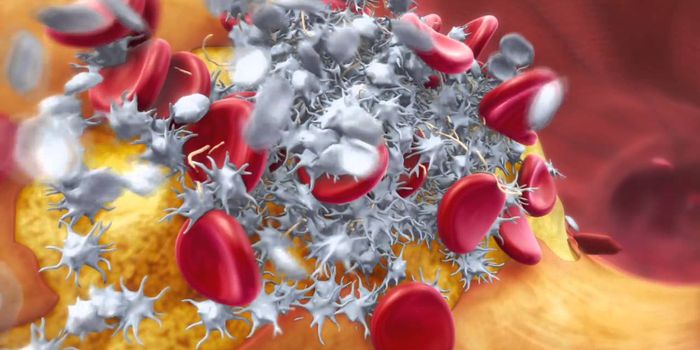

NOV 09, 2017CardiologyBlood clots are normally seen as something to be avoided, something with dangerous consequences such as heart attack, st ...

MAY 25, 2017CardiologyThe development of a blood clot could be very beneficial or very dangerous, depending on the situation. On one ha ...